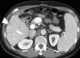

Liver infarct

A Zahn infarct is a pseudo-infarction of the liver, consisting of an area of congestion with parenchymal atrophy but no necrosis, and usually due to obstruction of a branch of the portal vein. Zahn infarcts are unique in that there is collateral congestion of liver sinusoids that do not include areas of anoxia seen in most infarcts. [Source: Wikipedia ]